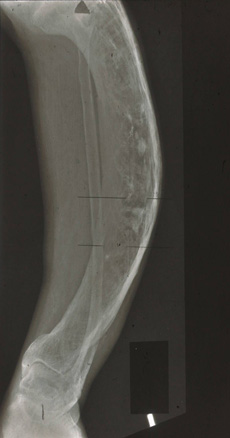

As radiografias do osso pagetoide afetado têm uma aparência clássica, com padrão trabecular grosseiro, córtices afinados e ruptura da interface trabecular/cortical.[Figure caption and citation for the preceding image starts]: Radiografia da doença de Paget do fêmur proximalDo acervo de Camilo Restrepo, Rothman Institute, Filadélfia, PA [Citation ends].

[Figure caption and citation for the preceding image starts]: Radiografia da doença de Paget da tíbiaDo acervo de Camilo Restrepo, Rothman Institute, Filadélfia, PA [Citation ends].

A pelve, os ossos longos e o crânio são os locais mais comuns de osso anormal.

Fraturas completas são incomuns, a menos que haja um leve trauma em um osso já comprometido.

estágio inicial: principalmente alterações líticas, observadas comumente no crânio; lesão lítica em forma de V avançando nos ossos longos; fraturas ocasionais, na maior parte, incompletas; estágio avançado: o quadro esclerótico predomina sobre o osteolítico